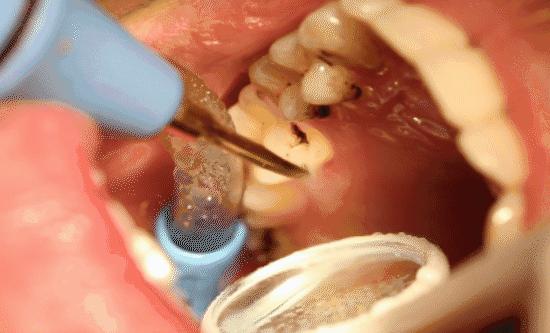

牙周炎的治疗方式之一